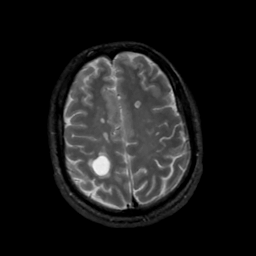

MR Study #5, March 10, 1991 -- Slice #39

[Home][Help][Clinical][Tour 1][Tour 2] Slice 39